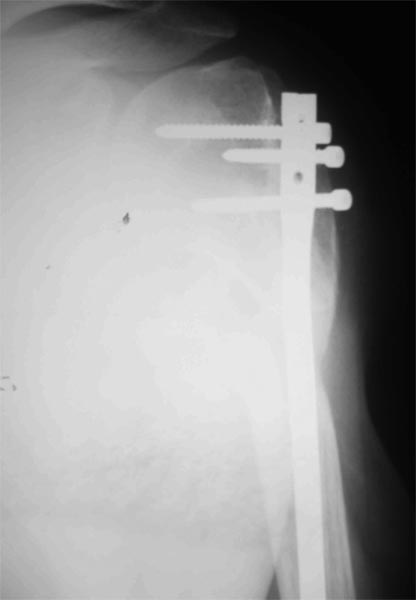

Уважаемые коллеги! Пациент получил травму около 1 года назад, выполнялся остеосинтез по поводу переломов лучевой, бедренной, плечевой костей. Обратился в связи с выраженной контрактурой в коленном суставе (сгибание 10-15 град)и практически отсуствием самостоятельного отведения плеча. Снимки представлены. Планируем выполнить реостеосинтез плеча (скорее всего этим же стержнем, так как другого нет) с коррекцией положения отломков в проксимальном отделе и сближением отломков в области диафиза. По надколеннику пока одна идея - его удаление. Хотелось бы услышать мнение и советы участников форума. - необходима ли будет костная пластика в области диафиза плеча? - адекватен ли по Вашему мнению реостеосинтез стержнем? - какая тактика в отношении ротационной манжеты? - приведет ли удаление надколенника и релиз сустава к существенному улучшению функции? Спасибо.

Надколенник-то, когда сломался? Не при редрессации-ли? Синтез плеча изначально сделан сикось-накось, надо переделывать, стержень - слишком длинный (видно вбили что есть), его использовать не удастся. То место, откуда торчит проксимальный конец стержня с винтами к вращательной манжете отношения не имеет - это немного выше, у бугорков. А что за радикализм в отношении надколенника? Удивляет то, что это пока единственная идея, пришедшая в голову автора;). Надо делать синтез, при этом и осуществить артролиз, а дальше видно будет.

Снимки бы почетче в обеих проекциях увидеть, и на всем протяжении - пока одна мутная проекция, дистального конца ни стержня, ни плечевой кости нет. Функциональные снимки делали, в максимальном отведении? Дефицит отведения только за счет варусной деформации, то есть проксимальный отдел плеча отводится нормально?

Как бы автор вопроса не убеждал себя, что в ситуации с гвоздем (его длиной, расположением относительно манжеты и бугорков и т.д.) все ясно, при таком качестве представленных рентгенограмм в единственной проекции никакой ясности быть не может.

В качестве примера - случай, который оперировал всего 2 недели назад, после похожего остеосинтеза, выполненного год назад. Пациентке 75 лет, тяжелый РА, легла для решения вопроса о ревизии тазобедренного сустава и заодно пожаловалась на то, что рука "крутиться" сама по себе, не поднимается. И болит, конечно. И посмотрите на разницу в информации на снимках головки плеча в двух противоположных проекциях. Даже комментировать ничего не нужно.